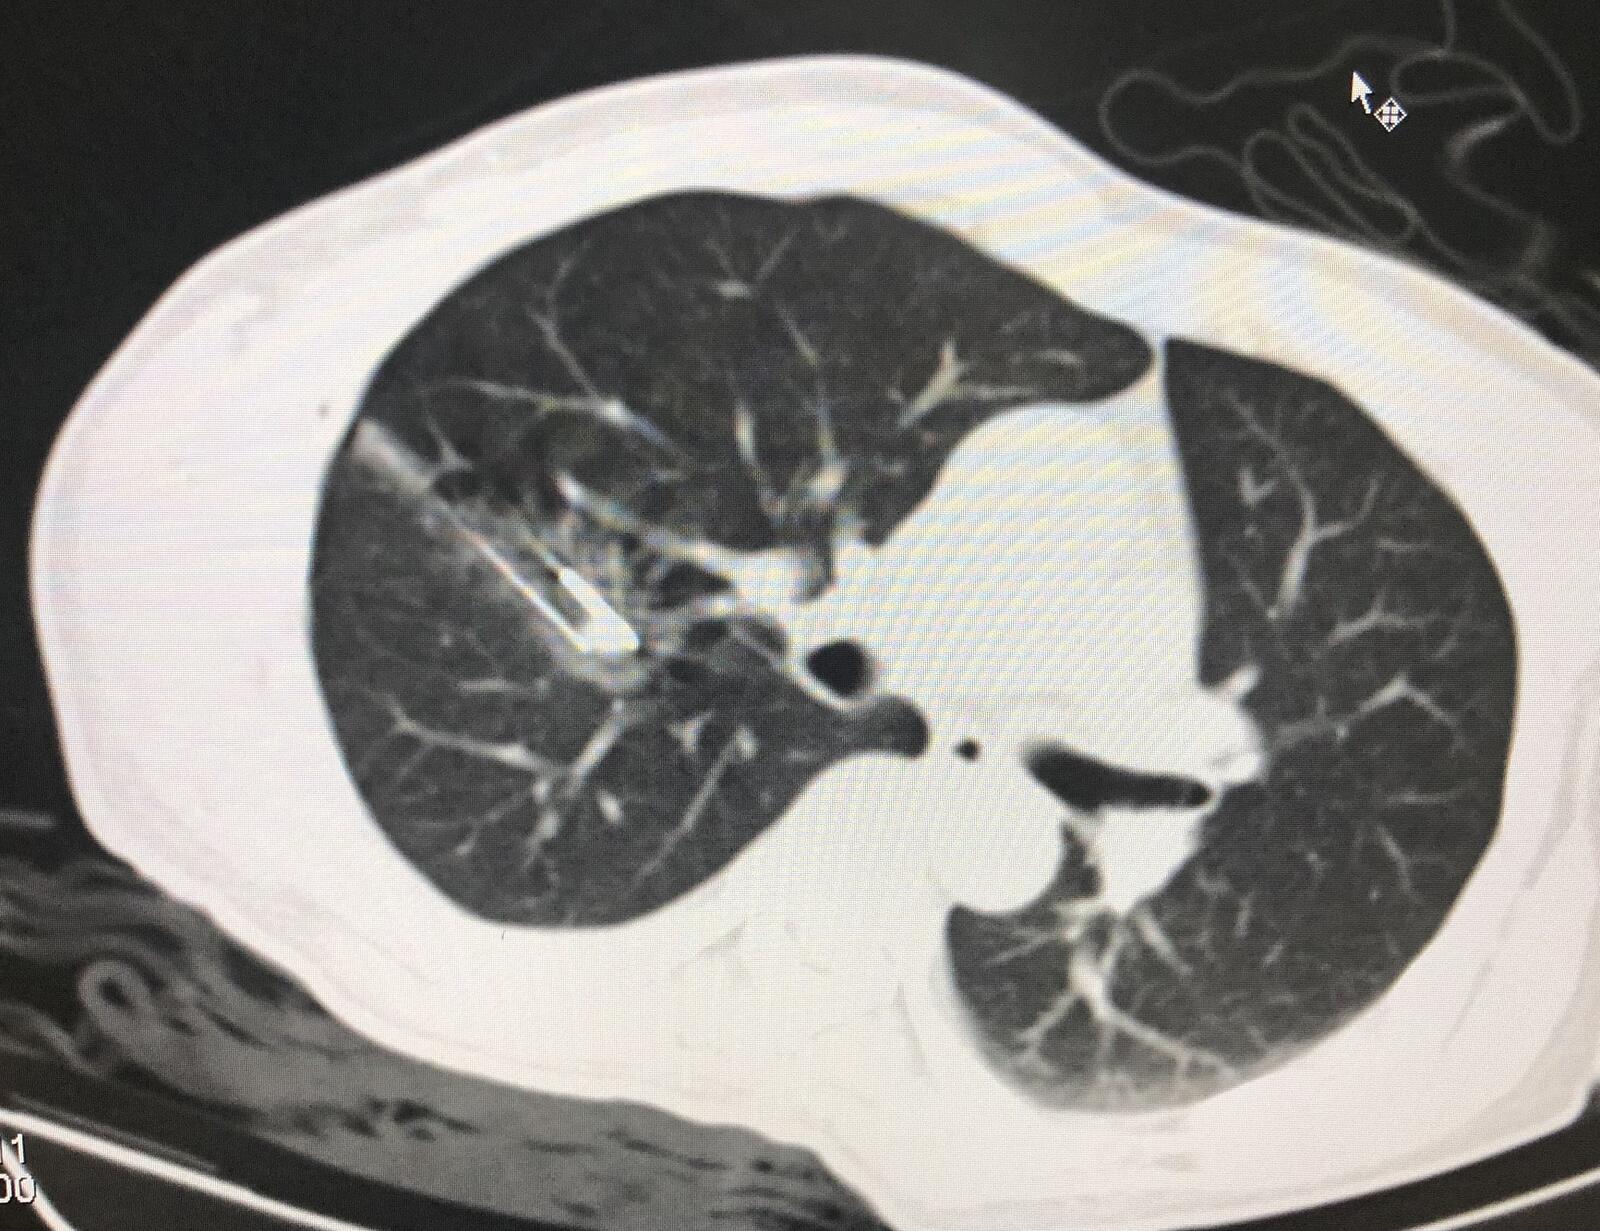

2.患者女性31岁,腺泡状软组织肉瘤术后肺转移,行微波消融治疗。

右肺转移瘤直径约1.3厘米,患者侧卧位。